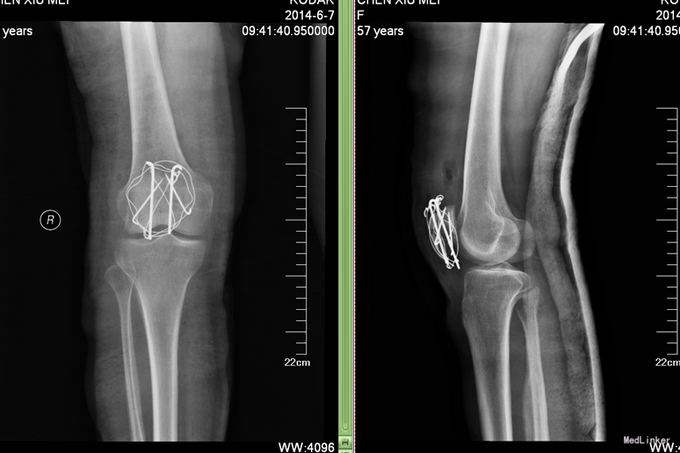

诊断:右髌骨骨折(气滞血瘀) 治疗:切开复位张力带固定。中医辨证论治:根据骨伤科三期辨证理论,早期因瘀血停滞影响骨痂生长,故以活血化瘀,消肿止痛为 主,应用桃红四物汤;中后期补益肝肾,补气养血,应用愈骨胶囊等药物应用。现患者属于骨折早期, 可运用桃红四物汤加减对症治疗,方药如下: 桃仁10g 红花10g 当归12g 川芎12g 赤芍12g 穿山甲6g 柴胡12g 黄芩10g 香附12g 延胡索15g 续断15g 生地12g 甘草6g 3剂 用法:每日一剂,水煎服400ml,分早晚两次温服。 中医调护:避风寒,慎起居,忌生冷,畅情志。

术后复查X线片示骨折复位良好,内固定在位且牢靠。根据骨伤科三期辨证理论,早期因瘀血停滞影响骨 痂生长,故以活血化瘀,消肿止痛为主,应用桃红四物汤。术后证属肝肾亏虚,气血不足,治以补益肝 肾,补气养血,应用愈骨胶囊等药物促进骨折愈合。术后嘱患者继续石膏托外固定,注意陪护,3月内扶 双拐、按指导患肢不负重功能锻炼;休息3个月,加强营养,促进骨折愈合;继续中药应用,促进骨折愈 合;定期复查,(1月、3月、6月);不适随诊。 本病例中医药应用结合手术复位,早期将骨折复位, 中医药早期应用活血化瘀、消肿止痛,可迅速缓解患者症状。中医药中后期应用可促进骨折愈合,加快 术后恢复,可使患者获得满意的术后疗效。